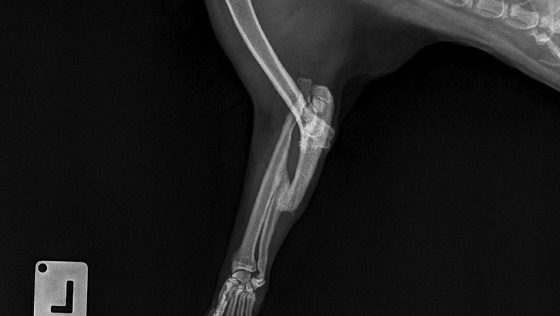

Pani doktor jaki jest stan Bucia na chwile obecną ? - Po wstepnej diagnostyce: Kot wykazuje bolesność przy poruszaniu łapką.Rozległość urazu jest bardzo duża. Pozostawianie łapki w takiej formie, jeśli chodzi o komfort poruszania się - nie jest najlepszym pomysłem. Co Pani radzi w tej sytuacji ?

- W wariancie minimum - można taką łapkę a m p u t o w a ć . I tak nie jest w stanie prawidłowo jej używać, a zlikwidujemy bolesność. A w wariancie maksymalnym jest do zrobienia bardzo dużo:

po 1 trzeba odświeżyć nieprawidłowo zrośnięte złamanie kości łokciowejpo 2 należy wydłużyć kończynę

po 3 trzeba ściągnąć chrząstki z powierzchni stawowej łokcia, bo jest już kompletnie zdegenerowana i na koniec po sforsowaniu przykurczu i zwłóknienia tkanek miękkich wykonalibyśmy artrodezę - czyli operacyjne usztywnienie stawu łokciowego w najbardziej optymalnej pozycji.Efekt jaki możemy tak uzyskać to zniesienie tej bolesności - optycznie będzie widać, że kot chodzi inaczej, ale nie będzie mu to tak dokuczało.

Pod warunkiem, że nie będzie żadnych nieprzewidzianych powikłań to leczenie przewidujemy na ok. 3 m-ce, z kosztami niestety przekraczającymi 1500 zł